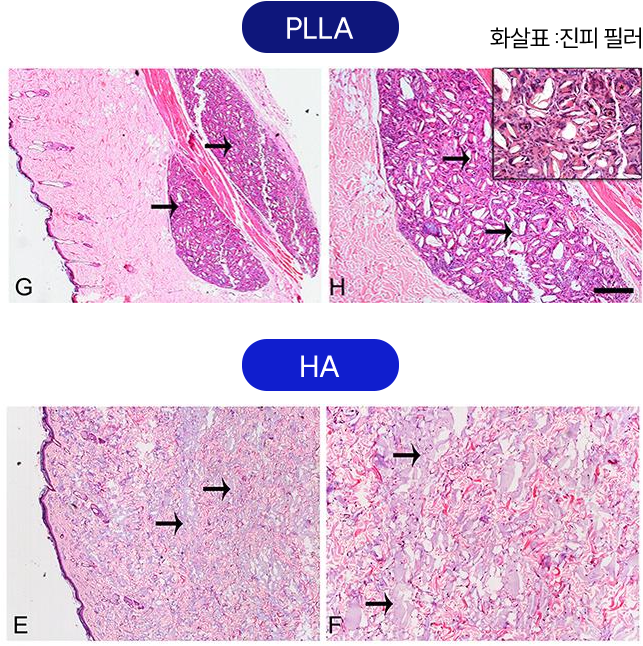

탄력 개선

탄력 개선